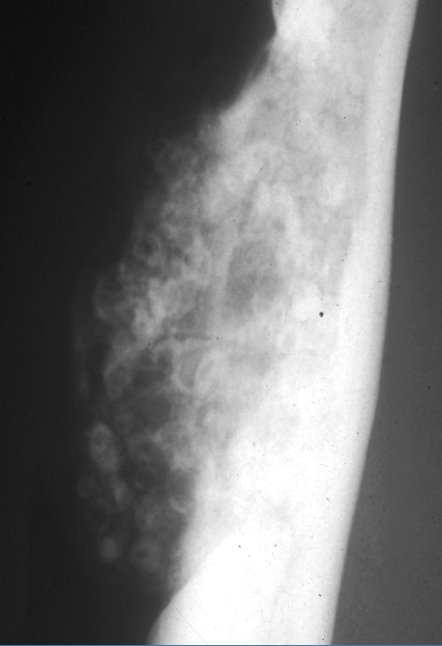

What is shown in this image?

A

osteosarcoma: